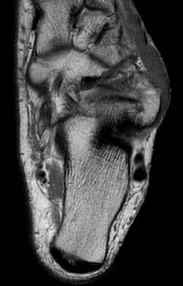

Figures 1a through 1c

Calcaneonavicular (CN) coalition

Talocalcaneal (TC) middle facet coalition

Tarsal coalitions occur when primitive mesenchymal cells fail to differentiate and form the

normal articular separations between the tarsal bones of the hindfoot. Overall incidence is difficult to determine because many affected people are minimally symptomatic or asymptomatic. Symptomatic tarsal coalitions typically present in adolescents as a painful flatfoot; however, there are a number of possible presentations, and occasionally symptoms do not appear until adulthood. Most tarsal coalitions are between the calcaneus and the navicular (CN) and the talus and the calcaneus (TC). Although most TC coalitions are across the middle facet, posterior facet coalitions do occur. Plain radiographic evaluation of suspected tarsal coalition is the mainstay for diagnosis. However, coalitions can be bony or fibrous, and making the diagnosis can be difficult. The addition of CT images to distinguish bony definition and MR images to decipher soft tissue can aid in diagnostics. Bony coalitions appear as definite bony bridging between the bones, while fibrous coalitions are suspected when distortion of the bony anatomy is seen. Bony coalitions are best seen on the oblique view (CN) and Harris axial view (TC). There are a number of secondary signs such as the anteater (AE) sign (elongation of the anterior process of the calcaneus as it extends to the navicular as seen on the lateral view [CN]). talar beaking (traction spur of the talar neck thought to result from abnormal stresses as seen on the lateral view [both CN and TN]), and the “C” sign (a continuous cortical contour from the medial talus to the sustentaculum tali [ST]) as seen on the lateral view (TC). A number of newer signs are not as well known, such as a broad mediolateral dimension of the navicular on the anteroposterior (AP) view (the

navicular is wider than the talar head [CN]), nonvisualization of the middle facet on the lateral view (TC), the brick sign (a normal ST is flat, but a distorted ST is enlarged and curved [CN]), and a tapered lateral navicular bone as seen on the AP view (the medial navicular [CN] is much thicker than the lateral navicular).

Figure 1a shows talar beaking (TB), an AE, and an open middle facet (MF). Figure 1b shows a wide navicular (WN), and Figure 1c shows an abnormal articulation between the calcaneus and the navicular, all consistent with a CN coalition.